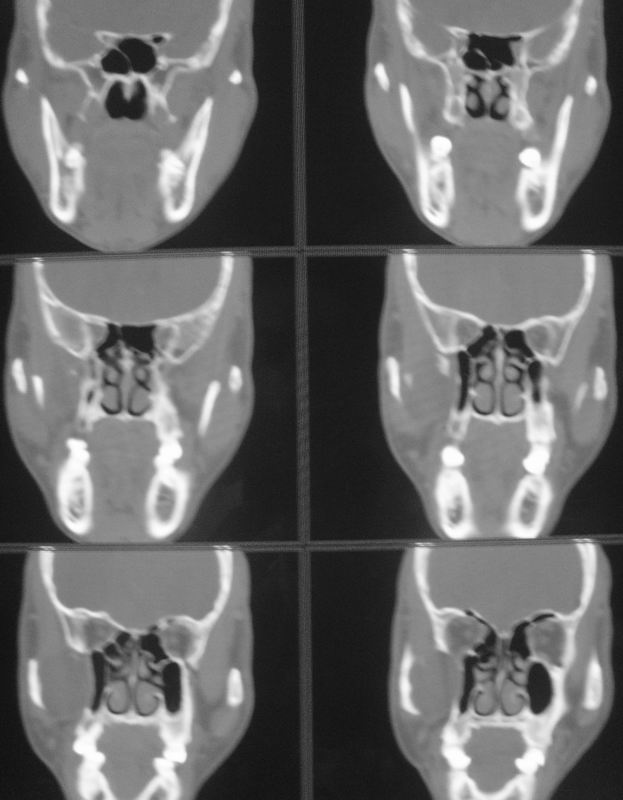

以下是引用zsl6918在2008-5-6 14:41:00的发言:[br]右侧颞下窝内囊性占位(增强未见强化),同侧上颌窦受压变形移位,提示慢性过程。右侧上颌骨局限性吸收破坏,提示良性病变。

以下是引用长城干红在2008-5-6 15:05:00的发言:[br]考虑:右侧颞下窝神经源性良性肿瘤。

以下是引用xuhuihong在2008-5-6 14:57:00的发言:[br]右侧颞下窝内囊性占位(增强未见强化),同侧上颌窦受压变形移位骨质吸收变薄,提示慢性过程。右侧上颌骨局限性吸收破坏,提示良性病变。考虑神经源性肿瘤可能,期待结果。